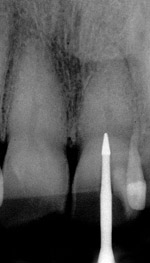

Fig. 21 Preoperative condition with normal calcification of tooth No. 8 and advanced calcific degeneration of the pulp of tooth No. 9.

Figure 21

Fig. 22 Radiograph with initial penetration of surgical length friction grip conical carbide bur. A slight redirection of the bur is indicated.

Figure 22